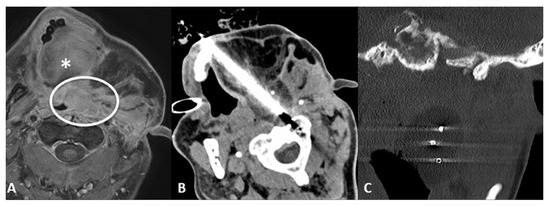

- Transglandular: This is a very useful approach in case of lesions in the pharyngeal space and prevertebral space, crossing the submandibular gland to reach these locations (Figure 3).